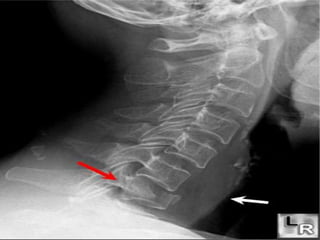

LATERAL VIEW

1. Anterior vertebral line (anterior

margin of vertebral bodies)

2. Posterior vertebral line

(posterior margin of vertebral

bodies)

3.Articular pillar (where superior

and inferior articular processes of

cervical vertebrae have fused on

either or both sides)

4. Spinolaminar line (posterior

margin of spinal canal)

5. Posterior spinous line (tips of

the spinous processes)

C1-C2

Predental space

(distance between posterior

aspect of anterior arch of C1

and anterior aspect of

odontoid process )



should be< 3mm In adult

and less <5mm in children

Or less

 ring sign of C2